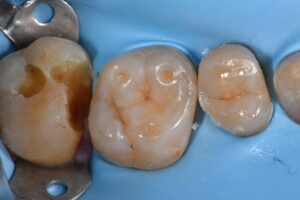

October 13, 2025 Direct Restoration #ClamplessDME #GarrisonCompositight #MajestyES2Universal Previous Post Next Post